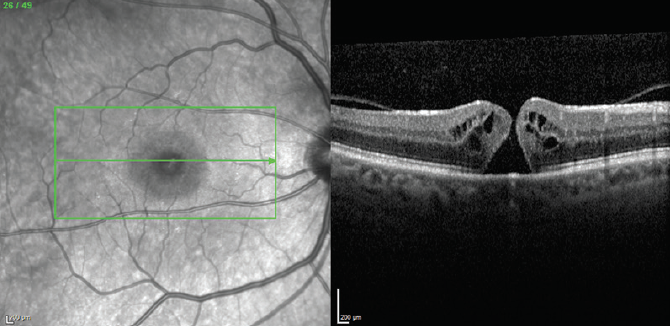

His fundus exam revealed macular edema OD; it was normal OS. Spectralis OCT (Heidelberg Engineering) high-speed 25-raster macular scans through, above, and below the fovea OD revealed macular edema and subretinal fluid (Figure 1). As the appearance was suggestive of a macular hole (MH), a high-density OCT scan was performed, revealing a small MH missed during the standard OCT scan (Figure 2).

<p>Figure 2. High-density OCT scan through the fovea demonstrating a small MH.</p>

Figure 2. High-density OCT scan through the fovea demonstrating a small MH.

Two lessons can be drawn from this case. First, standard OCT scans can miss a small MH. If there is a high degree of clinical suspicion that an MH is present based on other clinical features, a high-density scan through the fovea may reveal the hole.